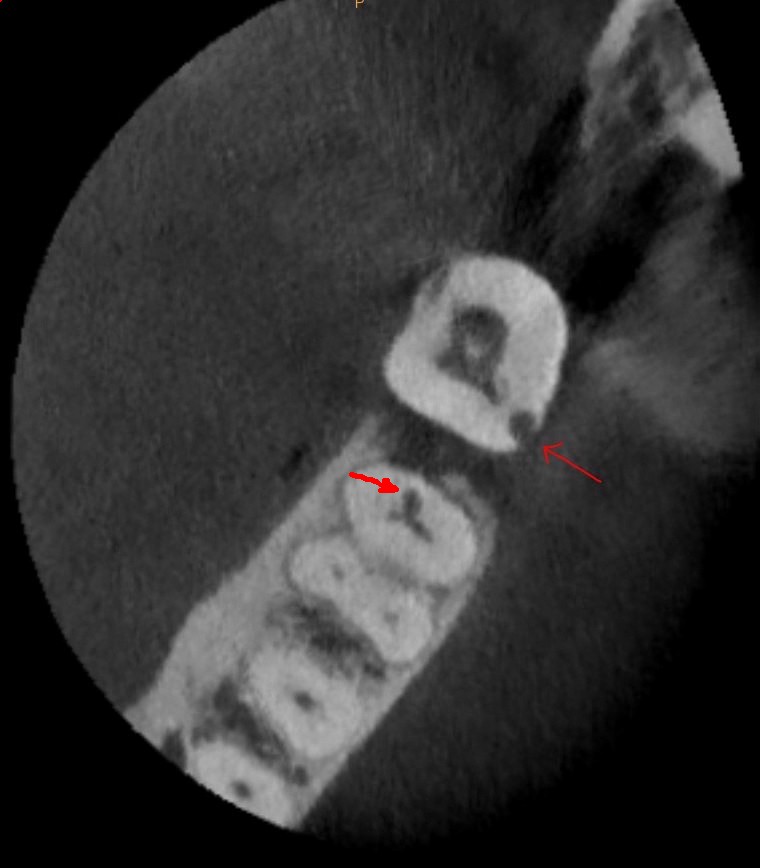

Pretreatment CBCT also assists with diagnosis and treatment when internal and external resorption presents. It is important to know the volume of tooth structure that has been affected by resorption and the exact location of the affected dentin, which can help determine if the tooth is structurally sound enough to initiate treatment, or if extraction is the best option (Figure 10).

4. Several cases, including endodontic retreatments, have healed in as little as 3-4 months (Figure 19 and Figure 20).

Fig 19. Preoperative 3D CBCT image before retreatment of tooth No. 14.

Figure 19

Fig 20. 3D CBCT image of tooth No. 14 at 4 months after single visit retreatment using multisonic ultracleaning technology.

Figure 20